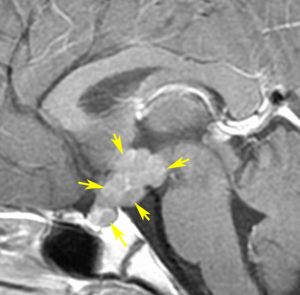

軽度の複視のみで発症した20代前半男性です。右上のように松果体腫瘍の前に割れ目が入るように第3脳室があり,両側視床に浸潤するために軽度の視床浮腫があり,ガドリニウムで強く増強され一部にのう胞があります。これだけでもgeriminomaにかなり特有の所見です。さらに,灰白隆起(矢印)のところに小さな神経下垂体germinoma腫瘍があります (bifocal tumor)。HCGは測定限界以下,AFP 2.5で,水頭症はありません。全ての臨床所見がgerminomaであることを示しています。

生検病理診断をしないでICE化学療法を1コース終えた後の画像です。腫瘍は消失しています。これでgerminomaであることが確認できたので,ICE化学療法を2コース追加して,25.2グレイの全脳室照射をして治療を終了しました。